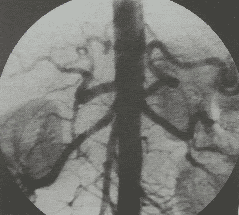

Tại vị trí can thiệp, bác sĩ sẽ tiến hành gây tê tại chỗ. Vị trí được chọn là từ động mạch đùi chung bên phải. Khi thuốc tê có tác dụng, bác sĩ sẽ chọc kim và đặt bộ mở động mạch vào động mạch đùi phải. Kế tiếp, dây dẫn, ống thông cũng sẽ được luồn vào lòng mạch, đưa vào động mạch thân tạng và động mạch tá tụy . Để xác định vị trí tổn thương chính xác và mức độ của miệng rách động mạch, bác sĩ sẽ dùng một lượng thuốc cản quang bơm vào mạch máu, toàn bộ hệ mạch chi phối cho tá tràng và tụy tạng sẽ được hiện rõ. Lúc này, một vi ống thông sẽ tiếp cận và chụp DSA chọn lọc động mạch có tổn thương.

Các đặc điểm của tổn thương trên mạch máu tá tụy sẽ được đánh giá đầy đủ một cách nhanh chóng. Bác sĩ sẽ dùng vi ống thông tiếp cận chọn lọc nhánh động mạch có tổn thương và tiến hành gây tắc mạch bằng các vật liệu phù hợp, có thể là cuộn dây kim loại hay keo sinh học. Khi các vật liệu này được bơm vào lòng mạch sẽ gây tắc mạch, tình trạng chảy máu sẽ chấm dứt.

Tuy nhiên, trước khi kết thúc, bác sĩ cần đánh giá sau can thiệp bằng cách chụp lại hệ thống động mạch chi phối tá tụy lại một lần nữa. Dưới màn hình chụp mạch số hóa xóa nền, các nhánh động mạch và tuần hoàn bàng hệ lưu thông bình thường, không có huyết khối. Đồng thời, bác sĩ cũng sẽ đánh giá tập trung nhất là vị trí chảy máu đã được can thiệp bít tắc hoàn toàn, không còn thông thương với hệ thống động mạch tá tụy hay không còn rỉ thuốc cản quang ra ngoài lòng mạch vào trong ổ bụng.